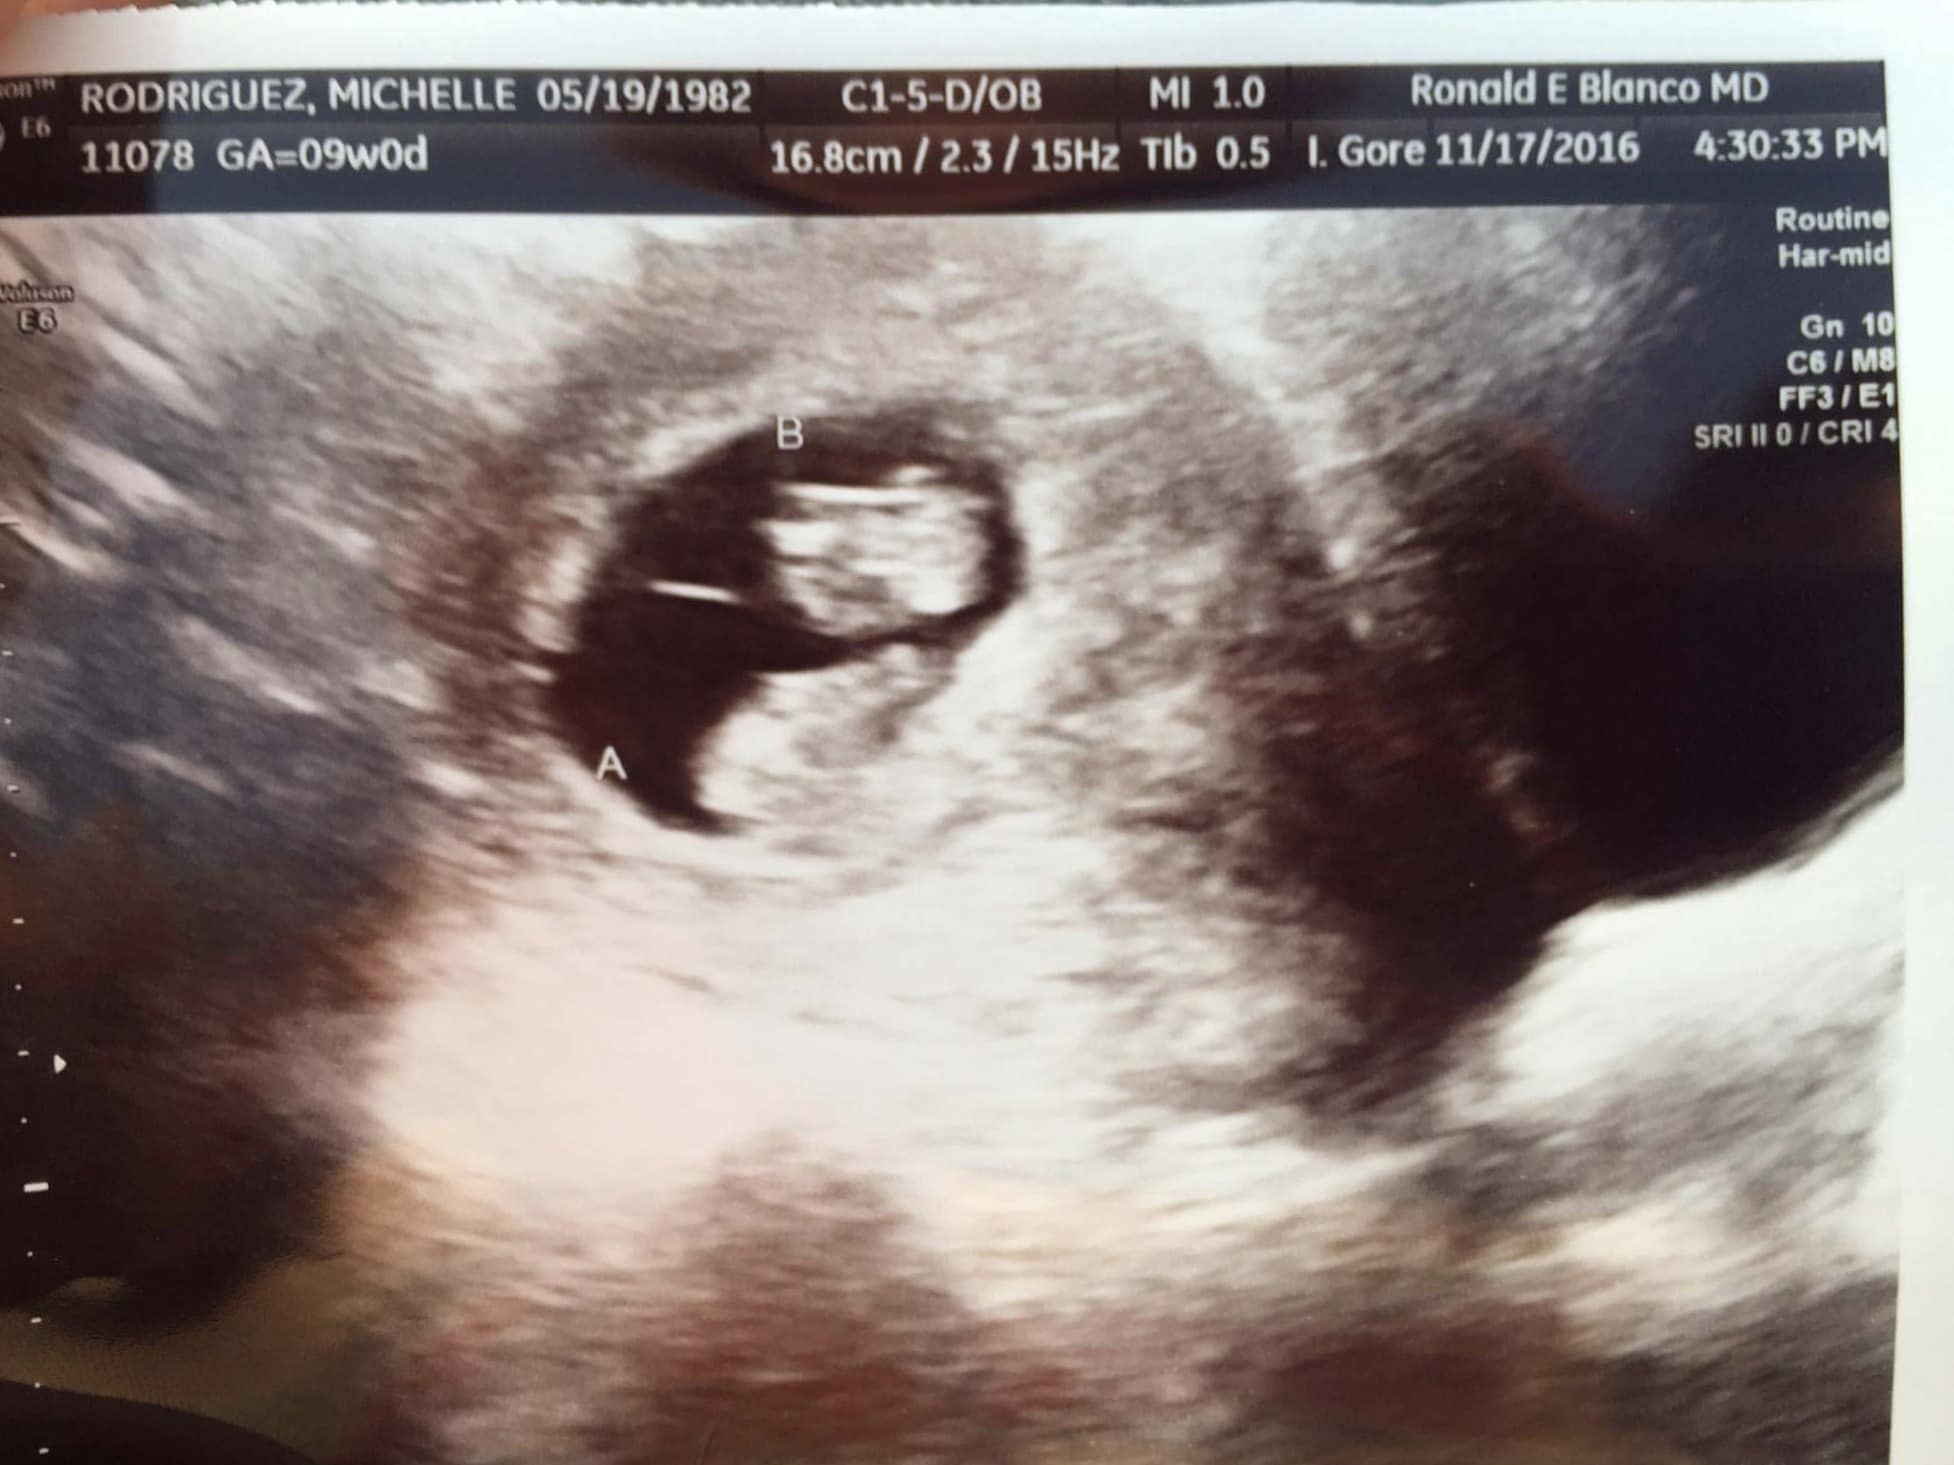

- Ultrasound Photos of 9 Weeks Pregnant With Twins

Ultrasound Photos of 9 Weeks Pregnant With Twins